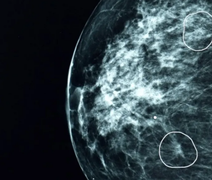

Cancêr de mama: A ferramenta de IA capaz de detectar tumores que passaram desapercebidos por médicos